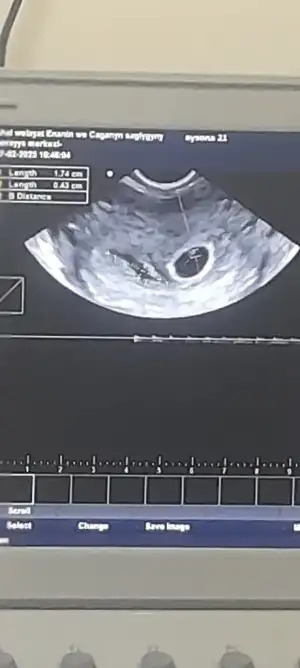

Evet gördüm çok şükür. Evett iyiki gitmiştim bu gün. İlk önce karından bakıldı bebek var yolunda ama yinede alttan bakalım dedi. Ve kanama alanı var dedi. Kanaman mi var dedi. Hayir deyince rahimde görünüyor dedi. Hemen gerkli şeyleri yazdırdım.

Kızlar bu kesenin yanındaki sm fan yazıyor ya onların hangisi kese mm si. Bana Dr söylemedi filanca santi falan diye

Lioo Lioo kese 1,7 cm görülüyor maşallah 🧿 ben de dün gittim keseler zat zor görüldü ya haftamız aynı seninle. Tüp bebek sanki bi tık geriden geliyo diye bişi hatırlıyorum inşallah öyledir.